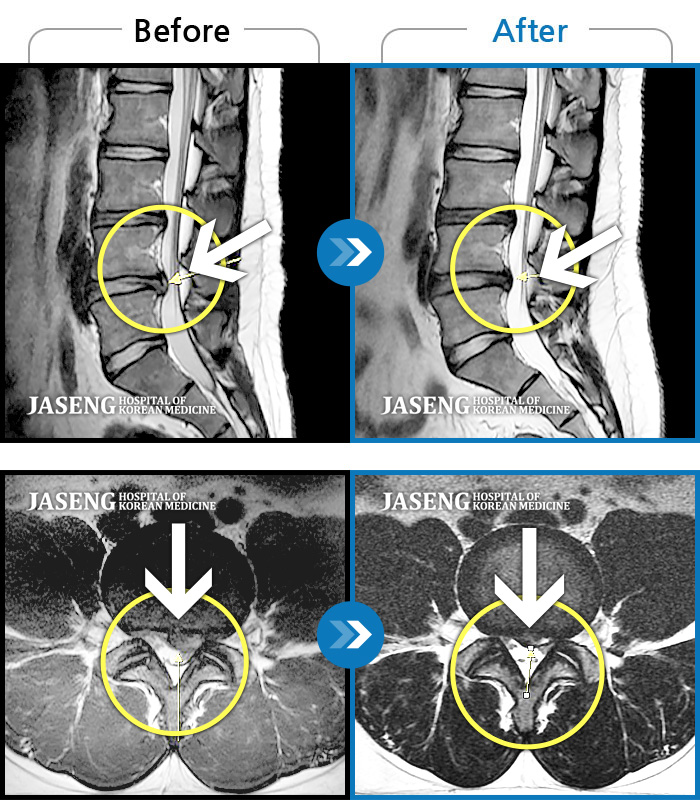

허리디스크

울산 · 정운석 원장

좌측 하지 외측이 저리면서 당김증상 및 감각둔화

촬영시기

2016.12.22 ~ 2022.11.24

2022.12.09